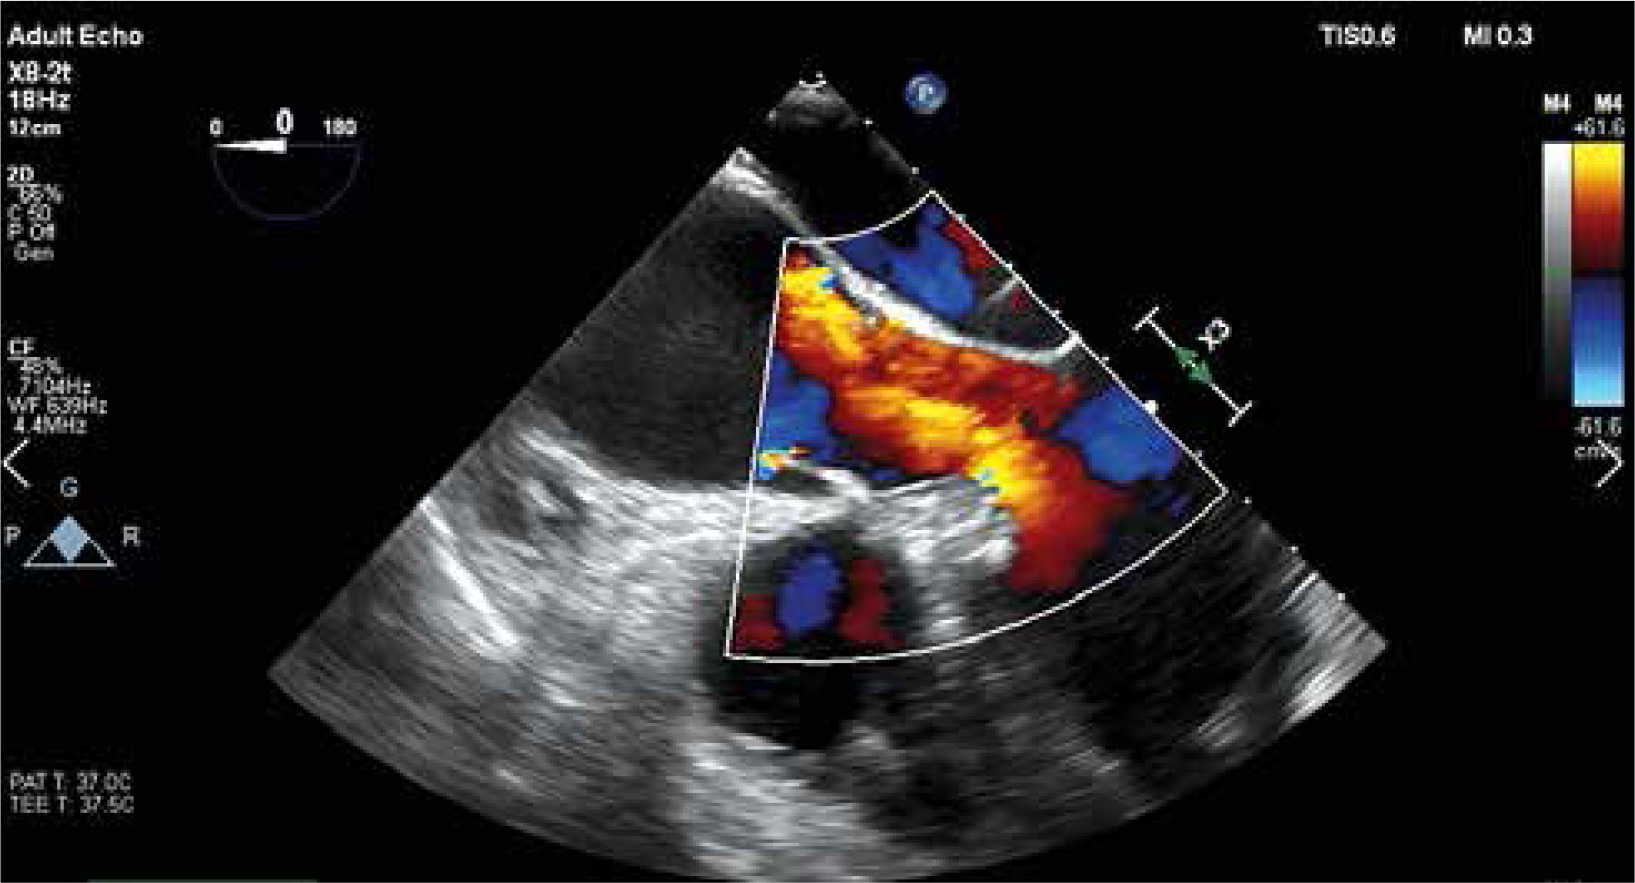

The key element of proper preparation of the patient for the surgery is the performance of chest computed tomography (CT) with 3D reconstruction to assess the ratio of the aneurysm to the sternum surface and the type of aortic position (right, central, left). Such assessment facilitates and streamlines the decision process about the skin incision site and the transverse cut of the sternum (Figure 1). Transesophageal echocardiography remains the most important functional examination in the assessment of aortic valve insufficiency and is essential in the intraoperative assessment of the competence of the performed reimplantation (Figure 2).

The competence of the aortic valve is checked again by transesophageal echocardiography. Careful and meticulous hemostasis is performed. BioGlue Surgical Adhesive (Jotec, Kennesaw, Georgia, United States) is used to buttress the suture lines. A bipolar electrode is placed for temporary stimulation at the anterior aspect of the RV outflow tract. The patient is weaned from extracorporeal circulation. The cannulas are removed and protamine sulfate is administered in a 1 : 1 ratio. A single 28F chest tube is inserted into the anterior mediastinum and exits under the xiphoid process. The pericardium is closed over the aorta. A gentamicin sponge is used for sternal wound infections prophylaxis. The breastbone is closed with three metal sutures. The subcutaneous tissue and the skin are closed in layers (Figures 8 and 9).